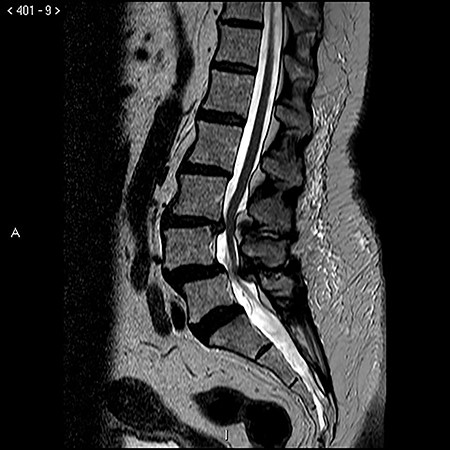

On exam, she exhibited weakness in her right iliopsoas, quadriceps, anterior tibialis and extensor hallucis longus muscle groups with pathologic hyperreflexia and markedly increased right lower extremity tone. Noncontrast lumbar spine MRI revealed L4–L5 anterolisthesis and a previously undiagnosed tethered cord with her conus medullaris extending to the L5–S1 level (Fig. 1), in addition to L3–L4 and L4–L5 central canal stenosis (Fig. 2A and B).

Preoperative T2 sagittal MRI demonstrating a tethered spinal cord continuing caudal to compression at L3–L4 and L4–L5 with the conus medullaris extending to L5–S1.